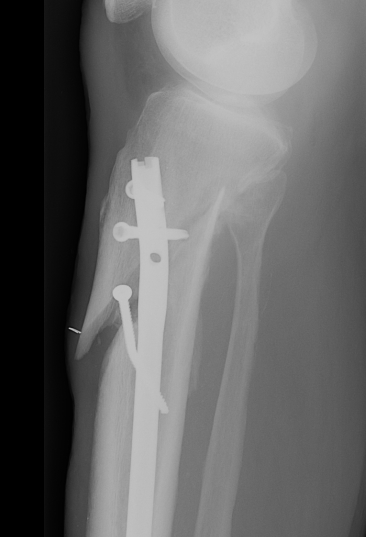

2. Blocking screws

- also lateral and posterior

- functionally narrow IM canal

- on concave side of deformity at the level of the fracture

- same positions as entry point

- posterior in proximal segment adjacent to fracture

- lateral in proximal segment adjacent to fracture

Smith and Nephew Tibial Meta Nail with Blocking Screws